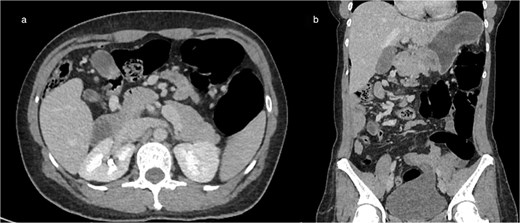

(a) Axial CT showing marked colonic distension upstream with an abrupt transition point in the right abdomen, consistent with mechanical obstruction related to volvulus (b) coronal CT reconstruction demonstrating colonic dilation and the corresponding transition zone.